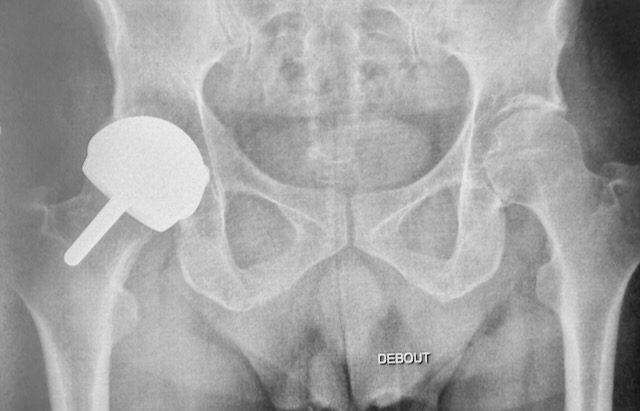

En fait, dans un resurfaçage, on remplace juste le cartilage abîmé et on garde la tête du fémur. On est donc au plus proche de l'anatomie!